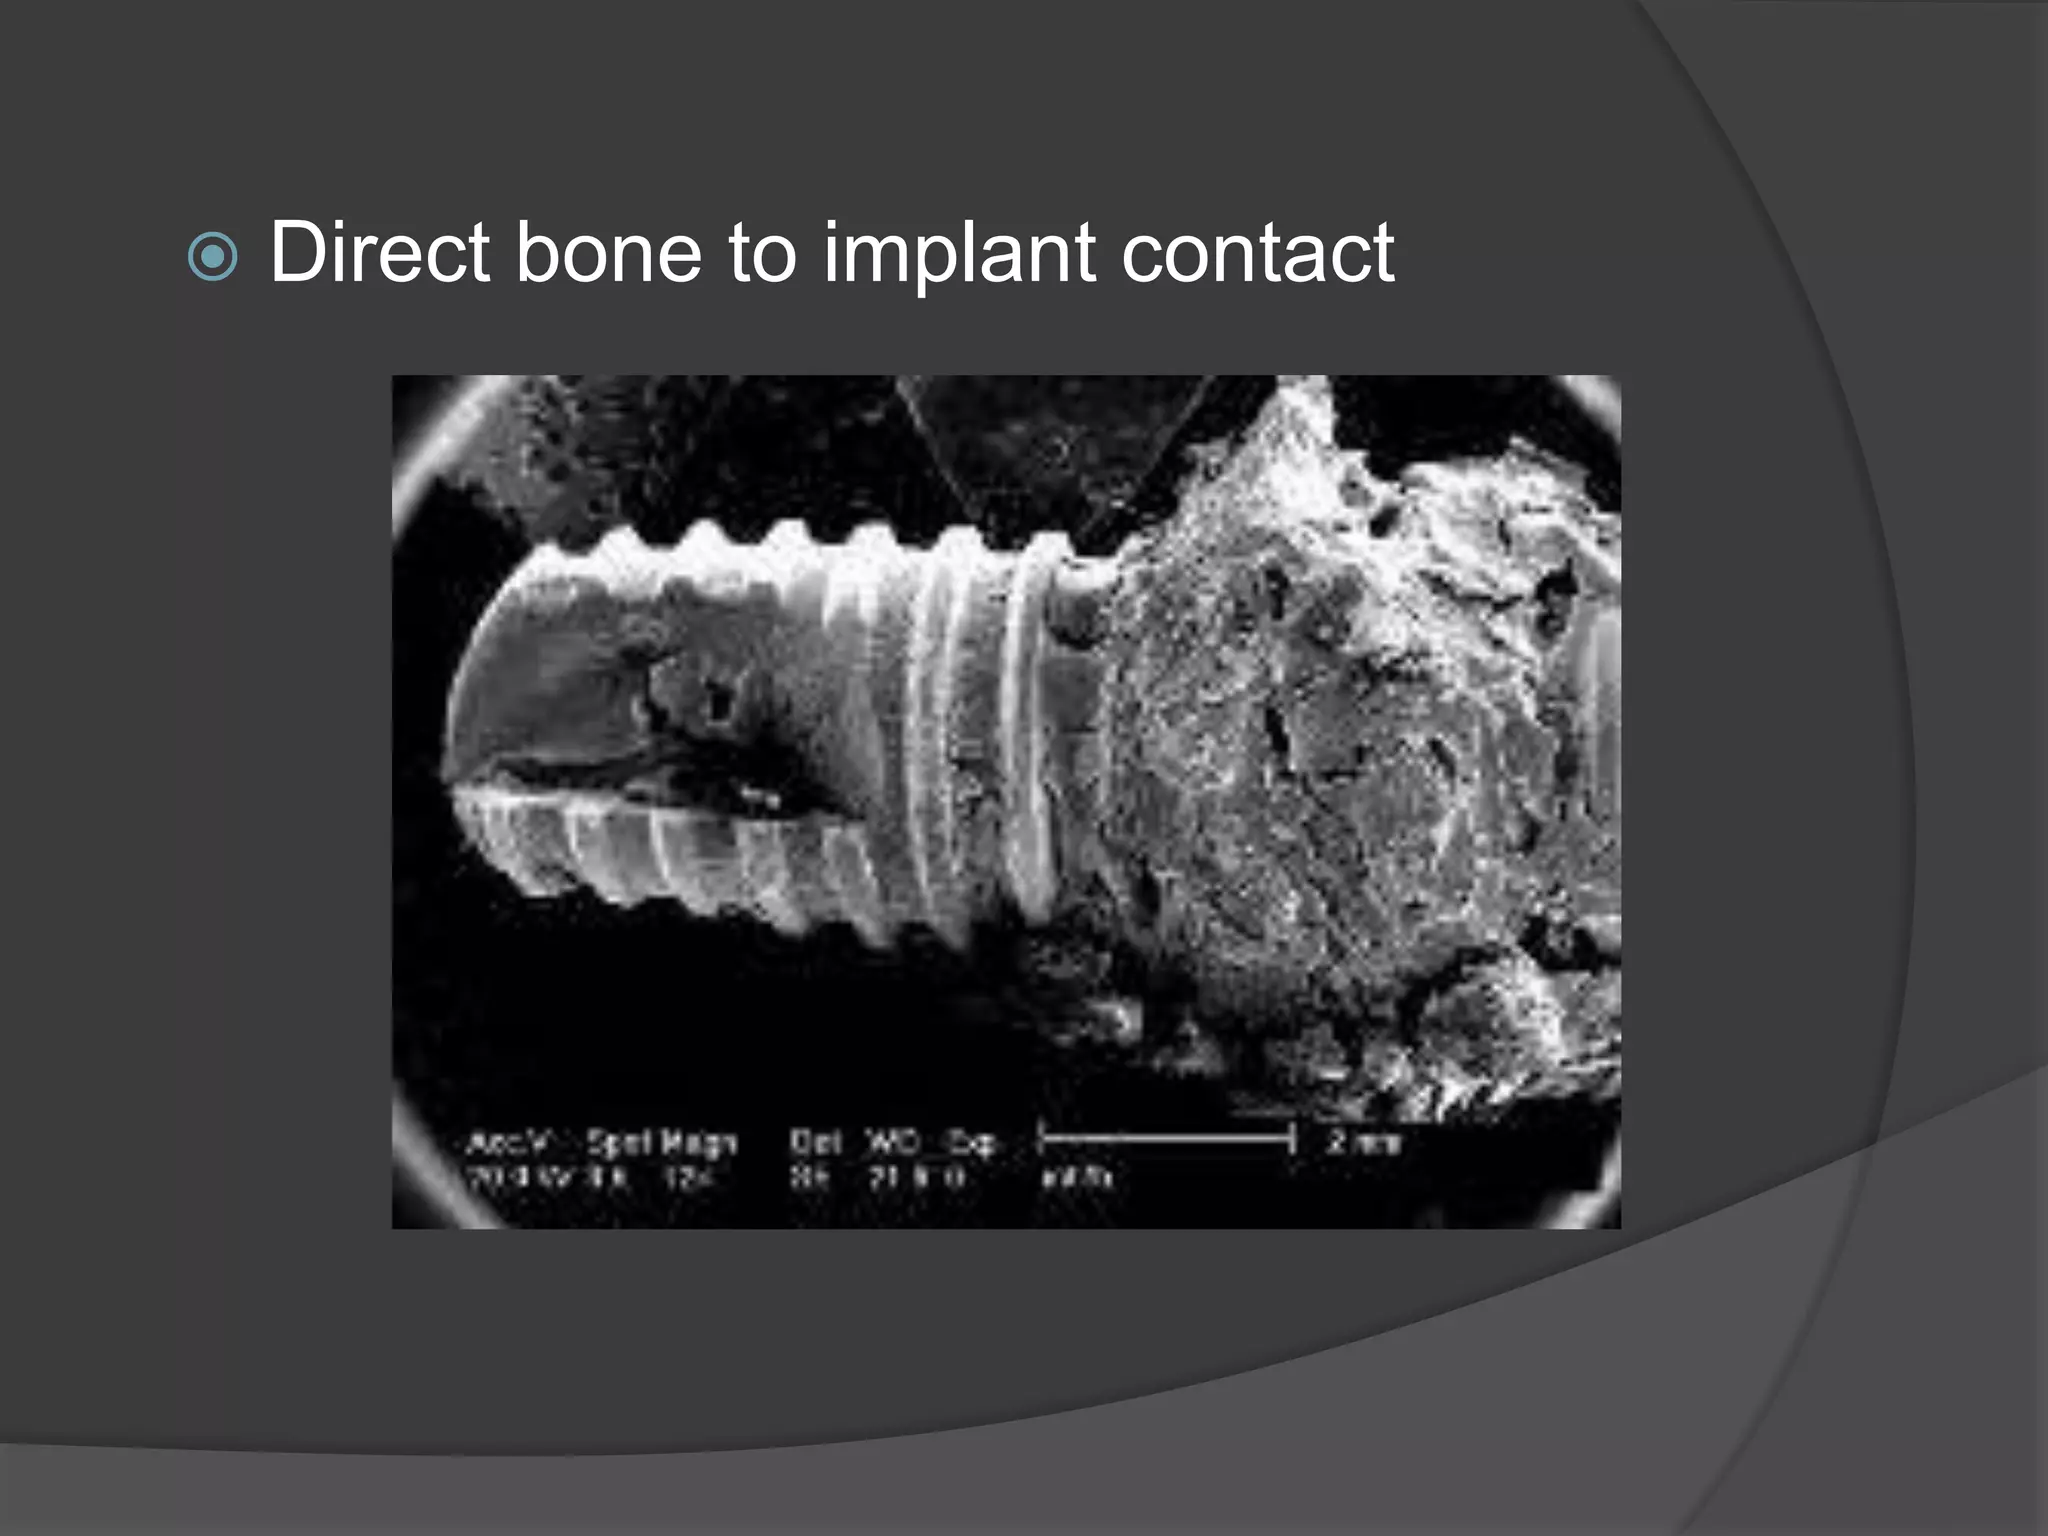

This document discusses factors that influence osseointegration and primary stability of dental implants, including implant design characteristics, surgical technique, and loading protocols. Specifically, it covers the processes of osseointegration and how forces on implants can either promote or inhibit bone remodeling. Key implant design considerations like length, diameter, threads, coatings and surface topography are analyzed in terms of their effects on stress distribution and bone-implant contact. The importance of primary stability and factors influencing it like bone quality and surgical skill are also addressed. Loading protocols ranging from immediate to conventional loading are compared.